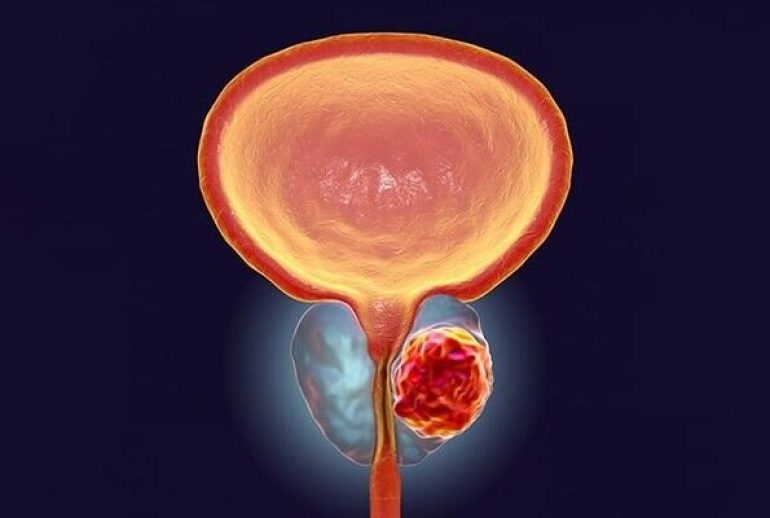

پروستات غدهای به اندازه یک گردو است که در زیر مثانه و جلوی رکتوم قرار دارد. وظیفه اصلی این غده تولید مایع منی است که به حفاظت و تغذیه اسپرمها کمک میکند. همچنین، پروستات در کنترل جریان ادرار نقش دارد.

پروستاتیت به التهاب غده پروستات گفته میشود. این التهاب میتواند ناشی از عفونت باکتریایی یا سایر عوامل باشد و باعث ایجاد درد و ناراحتی در ناحیه لگن شود.